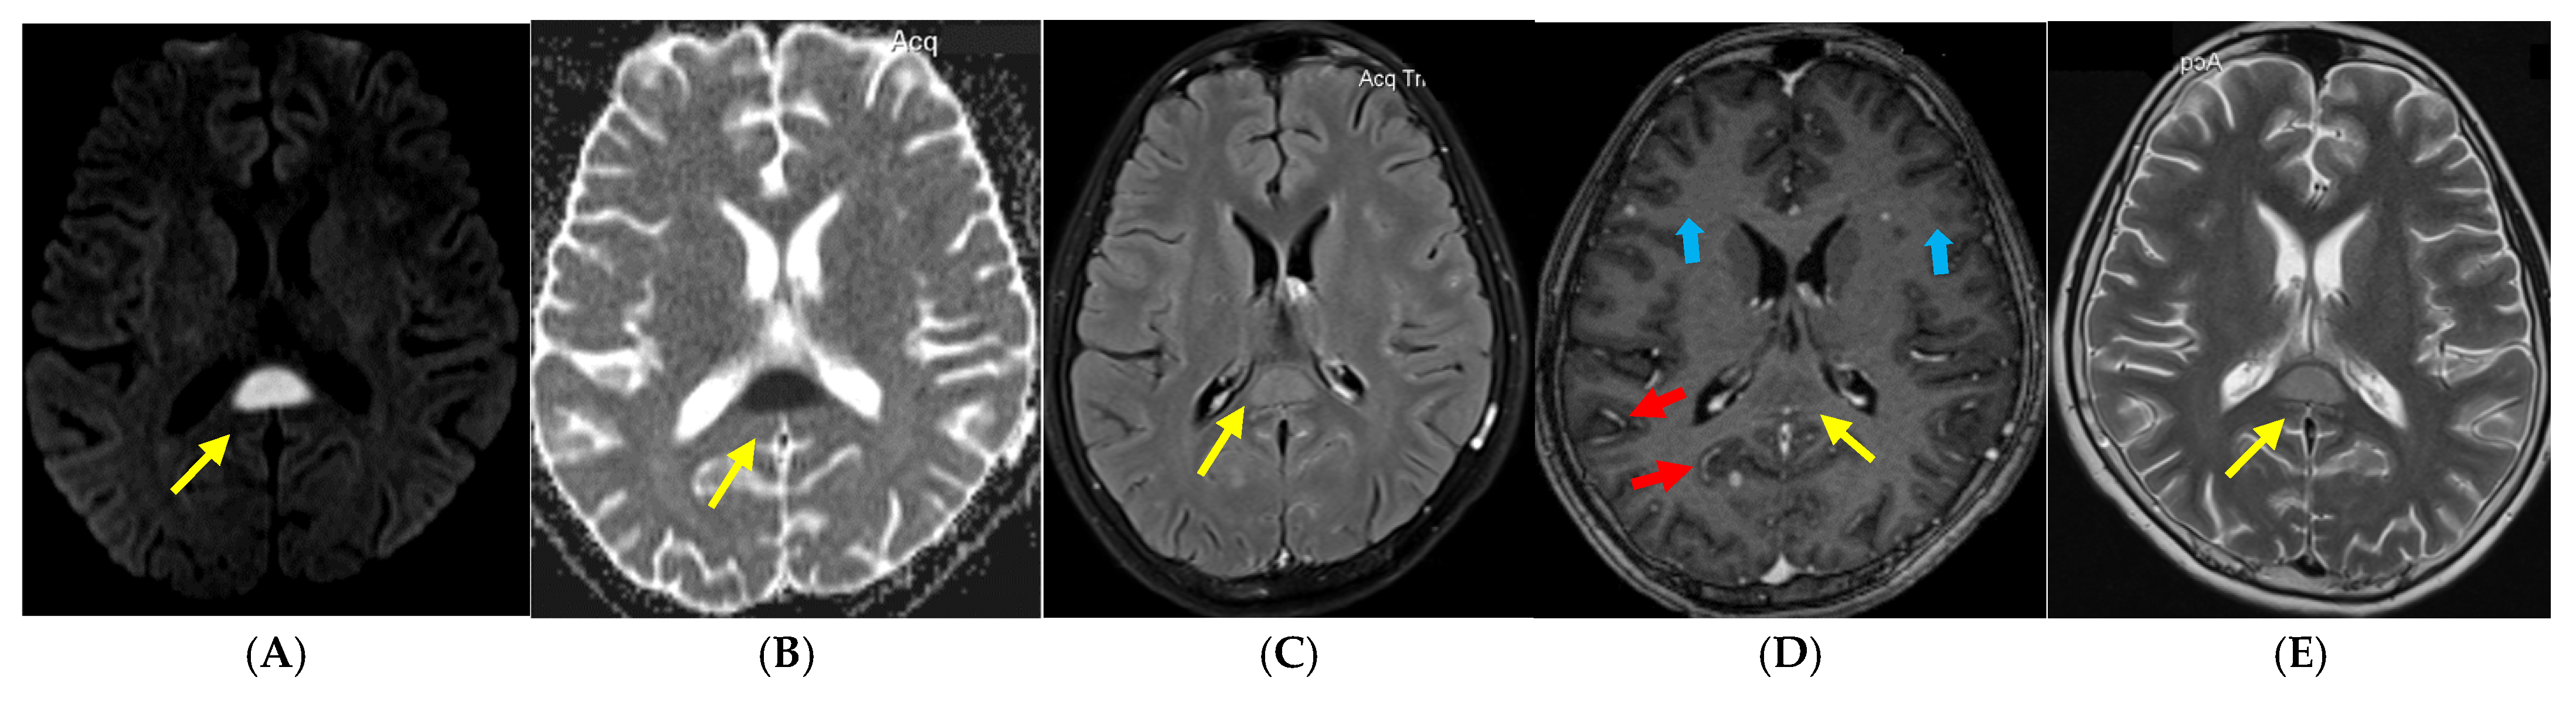

2. Case Report